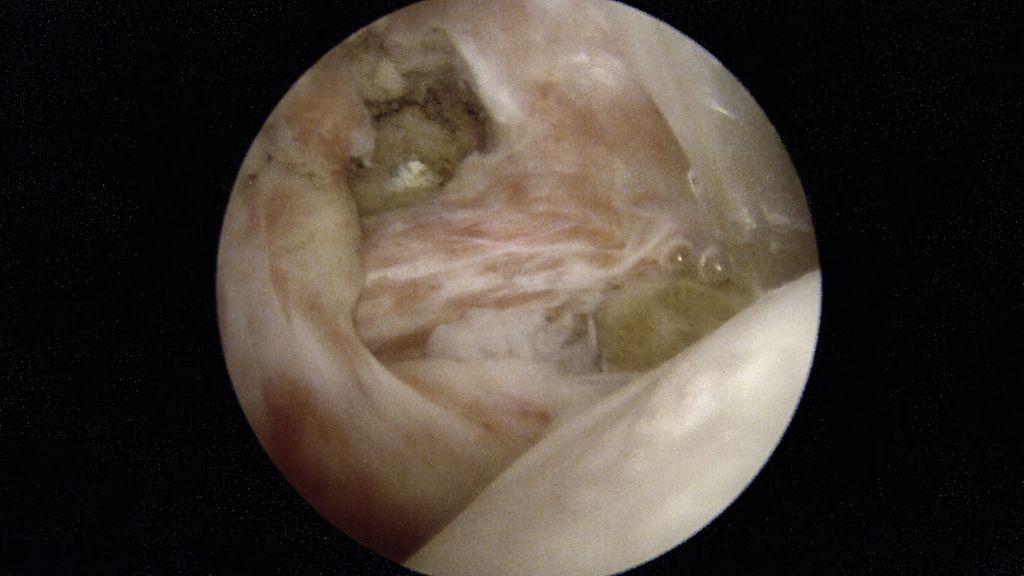

Abb. 1a, b: Dynamische Untersuchung mit klarer Instabilität der langen Bizepssehne (*) bei Supraspinatussehnenruptur

Besonders bei RM-Komplettrupturen treten Pathologien der langen Bizepssehne (LBS) in bis zu 89% der Fälle auf. Diese Veränderungen stehen oft im Zusammenhang mit chronischen Entzündungen oder degenerativen Prozessen, die entweder die Sehne mechanisch schwächen, destabilisieren oder eine Folge ihrer Überbelastung sein können.15 Insbesondere eine dynamische Untersuchung der Stabilität ist daher bei nicht sichtbaren Veränderungen obligat (Abb. 1). Eine gleichzeitige Bizeps-Tenodese im Rahmen einer RM-Rekonstruktion senkt die Wahrscheinlichkeit einer Revision der LBS um 35% und die einer generellen Revision innerhalb von vier Jahren um 23%.16 Daraus lässt sich ableiten, dass die adäquate Therapie von LBS-Läsionen das Risiko für eine Revisionsoperation reduziert.